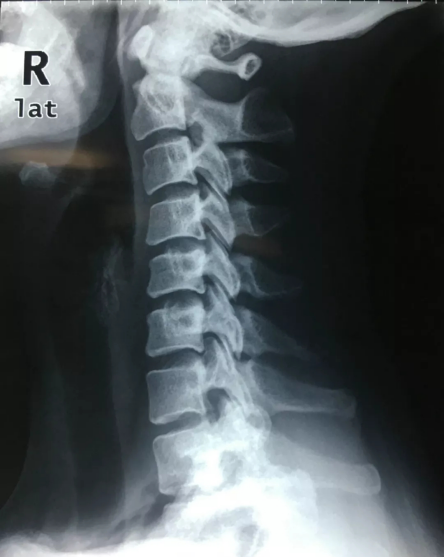

图:颈椎X光片侧面照,可以见到颈椎生理曲度反弓 图/张华

但是,有些人误解了这个姿势,继而引发了颈椎病。李女士从事会计行业快五年了,基于工作要经常低头的缘故,她颈椎病也没少犯。最近三个月,李女士的头晕、头痛又复发了。在广东省的第二中医院针灸康复科主任医师范德辉接诊李女士,用龙氏三步定位诊断,判断李女士是由于颈椎生理曲度反弓导致的颈椎不稳定。

于是,范德辉让李女士在治床上做了个“卧如弓”的姿势。结果当李女士示范完,范德辉就明白问题所在了——她误解了“卧如弓”,头部、颈部均弯曲,像只虾米,以至于颈椎生理曲度反弓,导致关节不稳定。

除李女士之外,相信还有很多人也犯了同样的错误。范德辉说,弓的两端是直的,而不是弯的。因此,真正的“卧如弓”,相对于弯曲的躯干而言,头颈跟足踝是直的。也就是说,晚上睡觉时,头颈的摆位跟正常站立位是一样的。只有这样,颈椎在休息的时候才依然保持中立位,才不会在白天已经“过度”屈曲的情况再继续保持屈曲,以致于颈椎曲度变直、反弓。